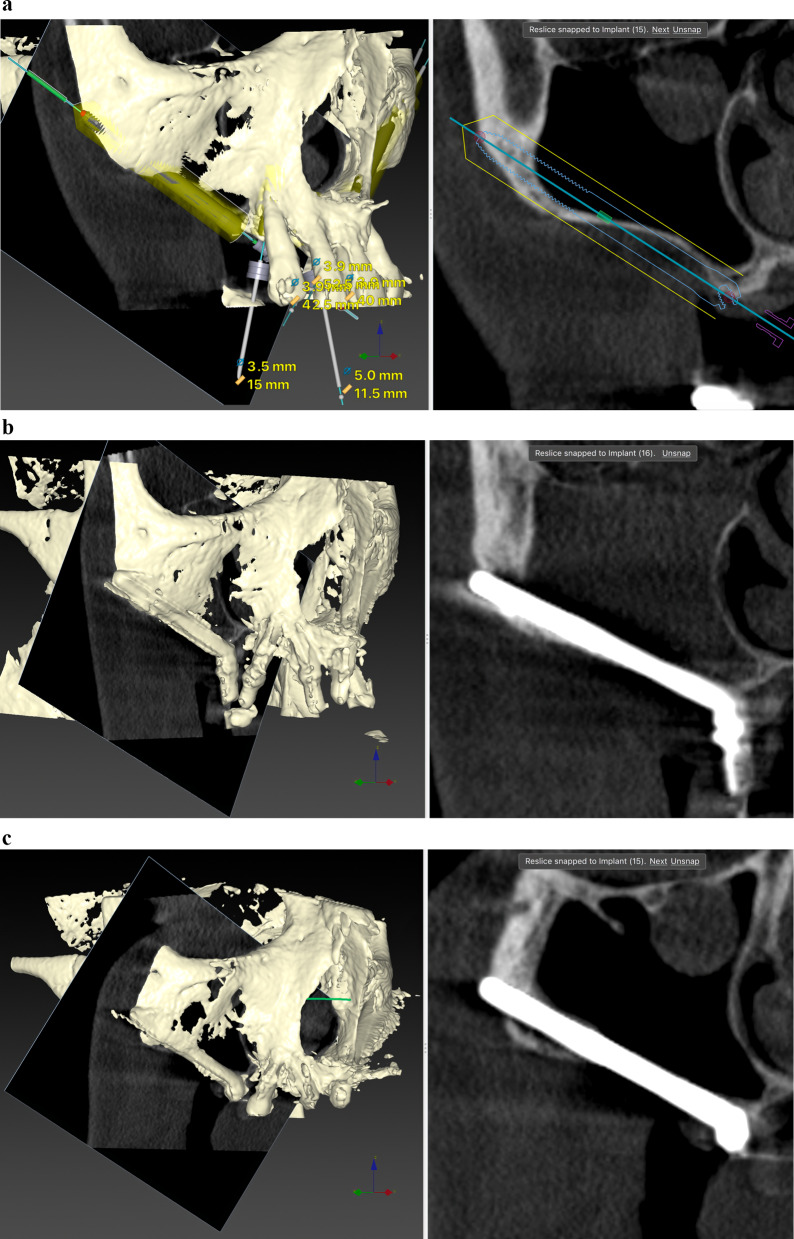

Results: Twenty patients were treated. Ten patients received two ZIs and regular implants; one received three ZIs plus regular implants, and nine received four ZIs. Fifty-nine ZIs were placed: thirty-six (61%) Straumann ZAGA-Flat implants and twenty-three (39%) Straumann ZAGA-Round implants. Four patients (20%) presented earlier sinus floor discontinuities. Fifteen patients (75%) had prior sinus opacities. Nineteen patients were followed for between 38 and 53 months (mean 46.5 months). One patient dropped out after 20 months. When comparing pre-surgical CBCT with post-surgical CBCT, 84.7% of the sites presented identical or less sinus opacity; nine locations (15%) showed decreased, and another nine increased (15%) post-surgical sinus opacity. Fifty-three ZIs (89.8%) maintained stable soft tissue. Six ZIs had recessions with no signs of infection. ZIs and prosthesis survival rate was 100%.